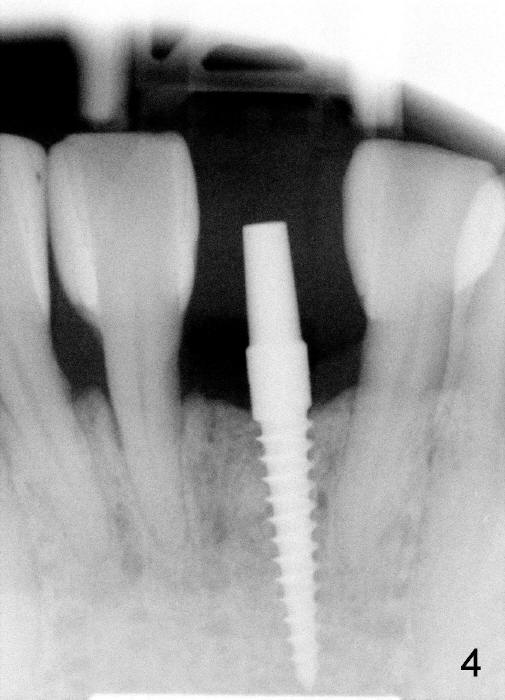

A 3x17 mm one piece implant is planned.  Osteotomy is created by a 1.5 mm pilot drill at the depth of 14 mm without incision (Fig.2); it is close to a neighboring incisor.  The trajectory of the osteotomy is intended to be changed (Fig.3 red) without success (white, 17 mm deep).  With measurement and calculation, the 3x17 mm implant is not expected to touch the root of the adjoining tooth.  In fact it is fine with insertion torque between 50-60 Ncm (Fig.4).  Without incision, the papillae appear to form immediately following implantation (Fig.5).  With adjustment of the abutment (Fig.6), an immediate provisional is fabricated (Fig.7).